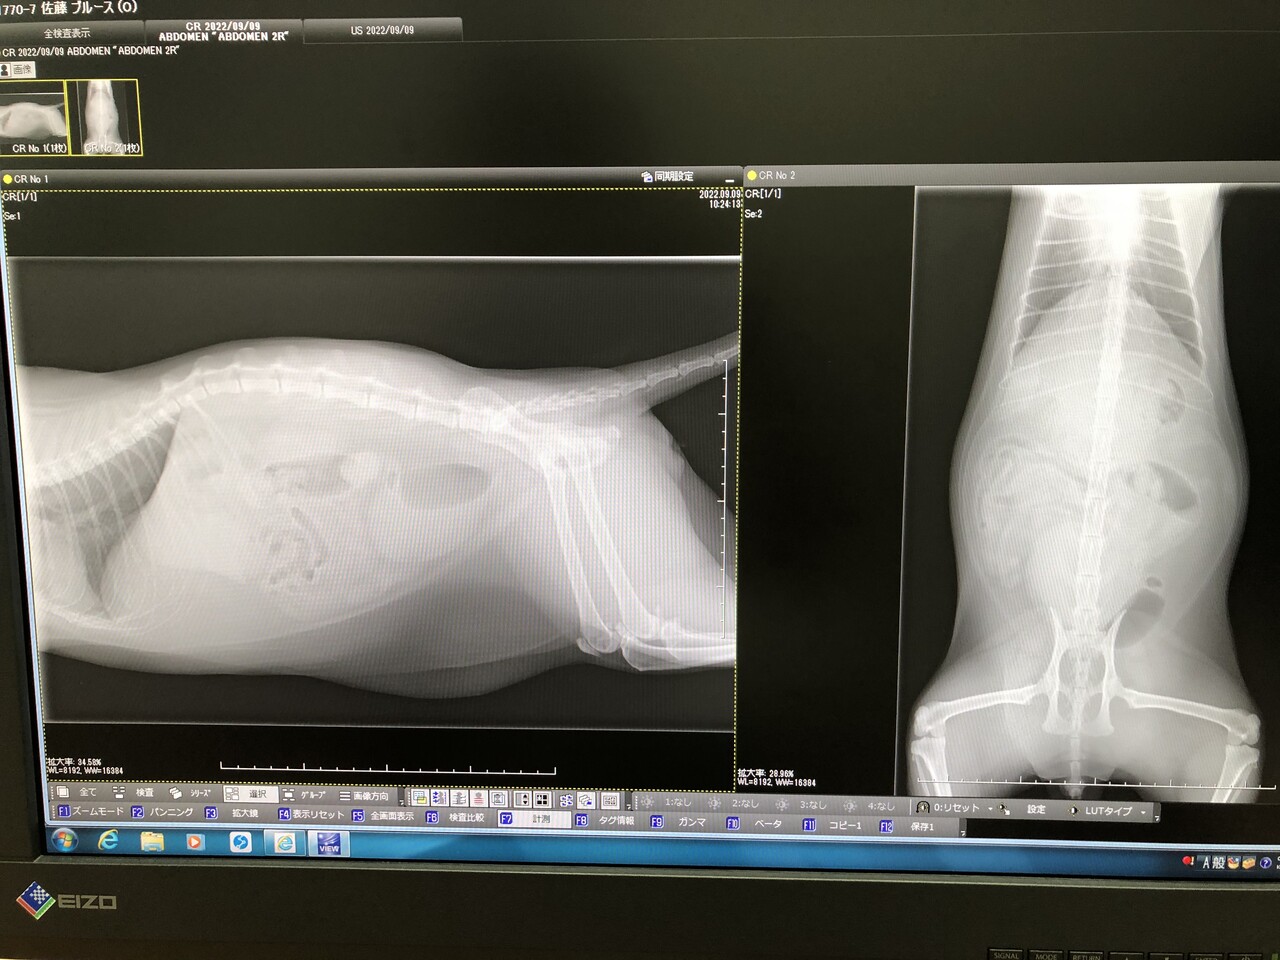

ストルバイトが原因でレントゲンの結果は石はなし。